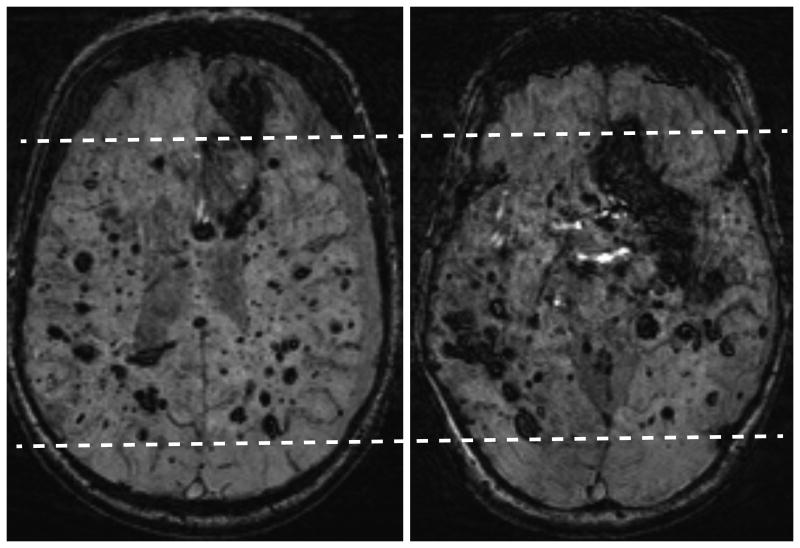

Patient 1 is a 46 year old man with genetically proven CCM1 mutation. He was treated in 1979 with a full course of therapeutic radiation in opposed lateral portals for a brainstem “mass,” likely an unrecognized CCM. His current brain MRI (Figure 1 A and B) reveals more than 500 CCMs.

Figure 1.

A (left) and B (right): Susceptibility-weighted MRI axial images show extensive CCM burden (both large and small) in the brain with relative sparing of the anterior and posterior cerebrum, indicating a central brain radiation port was used (dashed lines). As a result of his extensive disease burden, this patient has poor neurological function, residing in a group home and using a walker for ambulation. There is a chronic left subdural hematoma caused by lack of coordination and balance with numerous related falls.